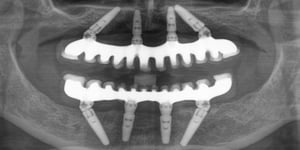

All-on-4 je implantološka metoda rješavanja bezubosti kod koje se cijeli zubni luk nadomješta fiksnim mostom na četiri implantata, u gornjoj ili donjoj čeljusti.

Kompjuterski vođena implantologija i digitalna tehnologija omogućuju preciznu ugradnju implantata i privremeni protetski rad u jednoj posjeti, a trajni most postavlja se nakon 3 do 6 mjeseci cijeljenja.

Cijeli zubni luk nadomješta se fiksnim mostom na četiri implantata, a privremeni protetski rad dobivate u jednoj posjeti, što znatno skraćuje put do novog osmijeha.